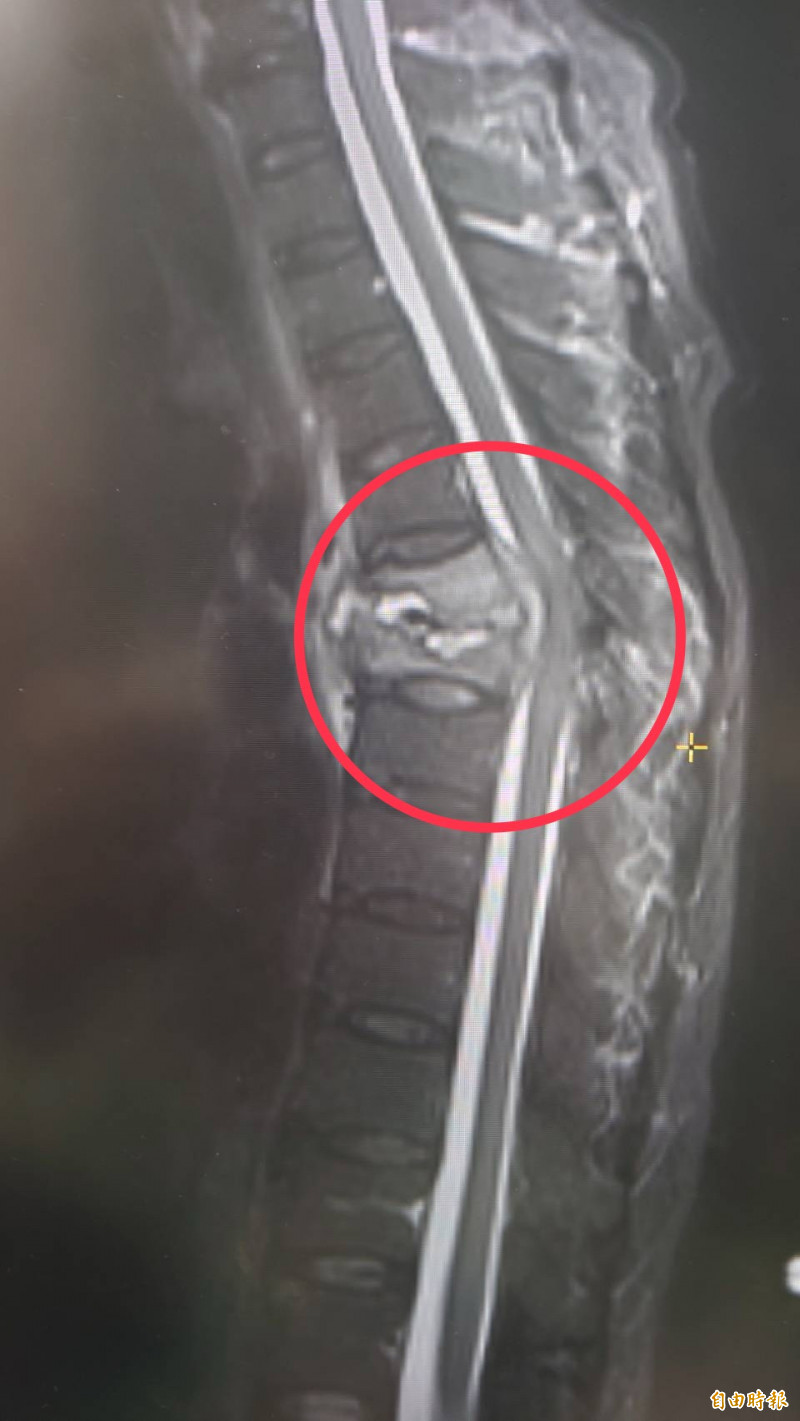

部立台中醫院神經外科主任陳典廷表示,婦人的胸椎第5、6節壓迫性骨折,骨折處有顆約3公分大膿包,壓迫脊髓神經,進行清創手術合併抗生素整合治療,住院兩週後出院可走路,目前戴著背架,持續接受抗生素治療,待感染控制穩定後,準備再行胸椎固定手術。